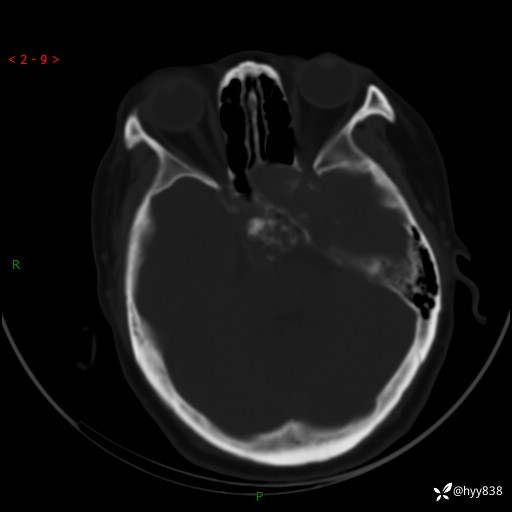

老年女性,视力下降3年。鞍区钙化性肿块,鉴别诊断有哪些---(有结果)

简要病史:患者3年前无明显诱因左眼出现视力下降,出现视物模糊,无头痛,无头晕,无恶心、呕吐,无意识障碍,无肢体麻木及抽搐,无心慌、胸闷,无腹痛、腹胀等不适,无旋地转感。个月前右眼视力下降,患者视物模糊逐渐下降,自诉看东西有雾感。在当地医院眼科就诊,症状无好转,行头部MR提示:鞍区肿物。现患者为求诊治来我科就诊,在当地市中医医院行头部CT:提示鞍区占位。患者现求进一步诊治来我院就诊,门诊以“鞍区肿物”收入我科。 患病以来,患者精神、饮食、睡眠尚欠佳,大小便如常,体力体重无明显变化。

临床诊断:鞍区肿物

颅脑CT平扫